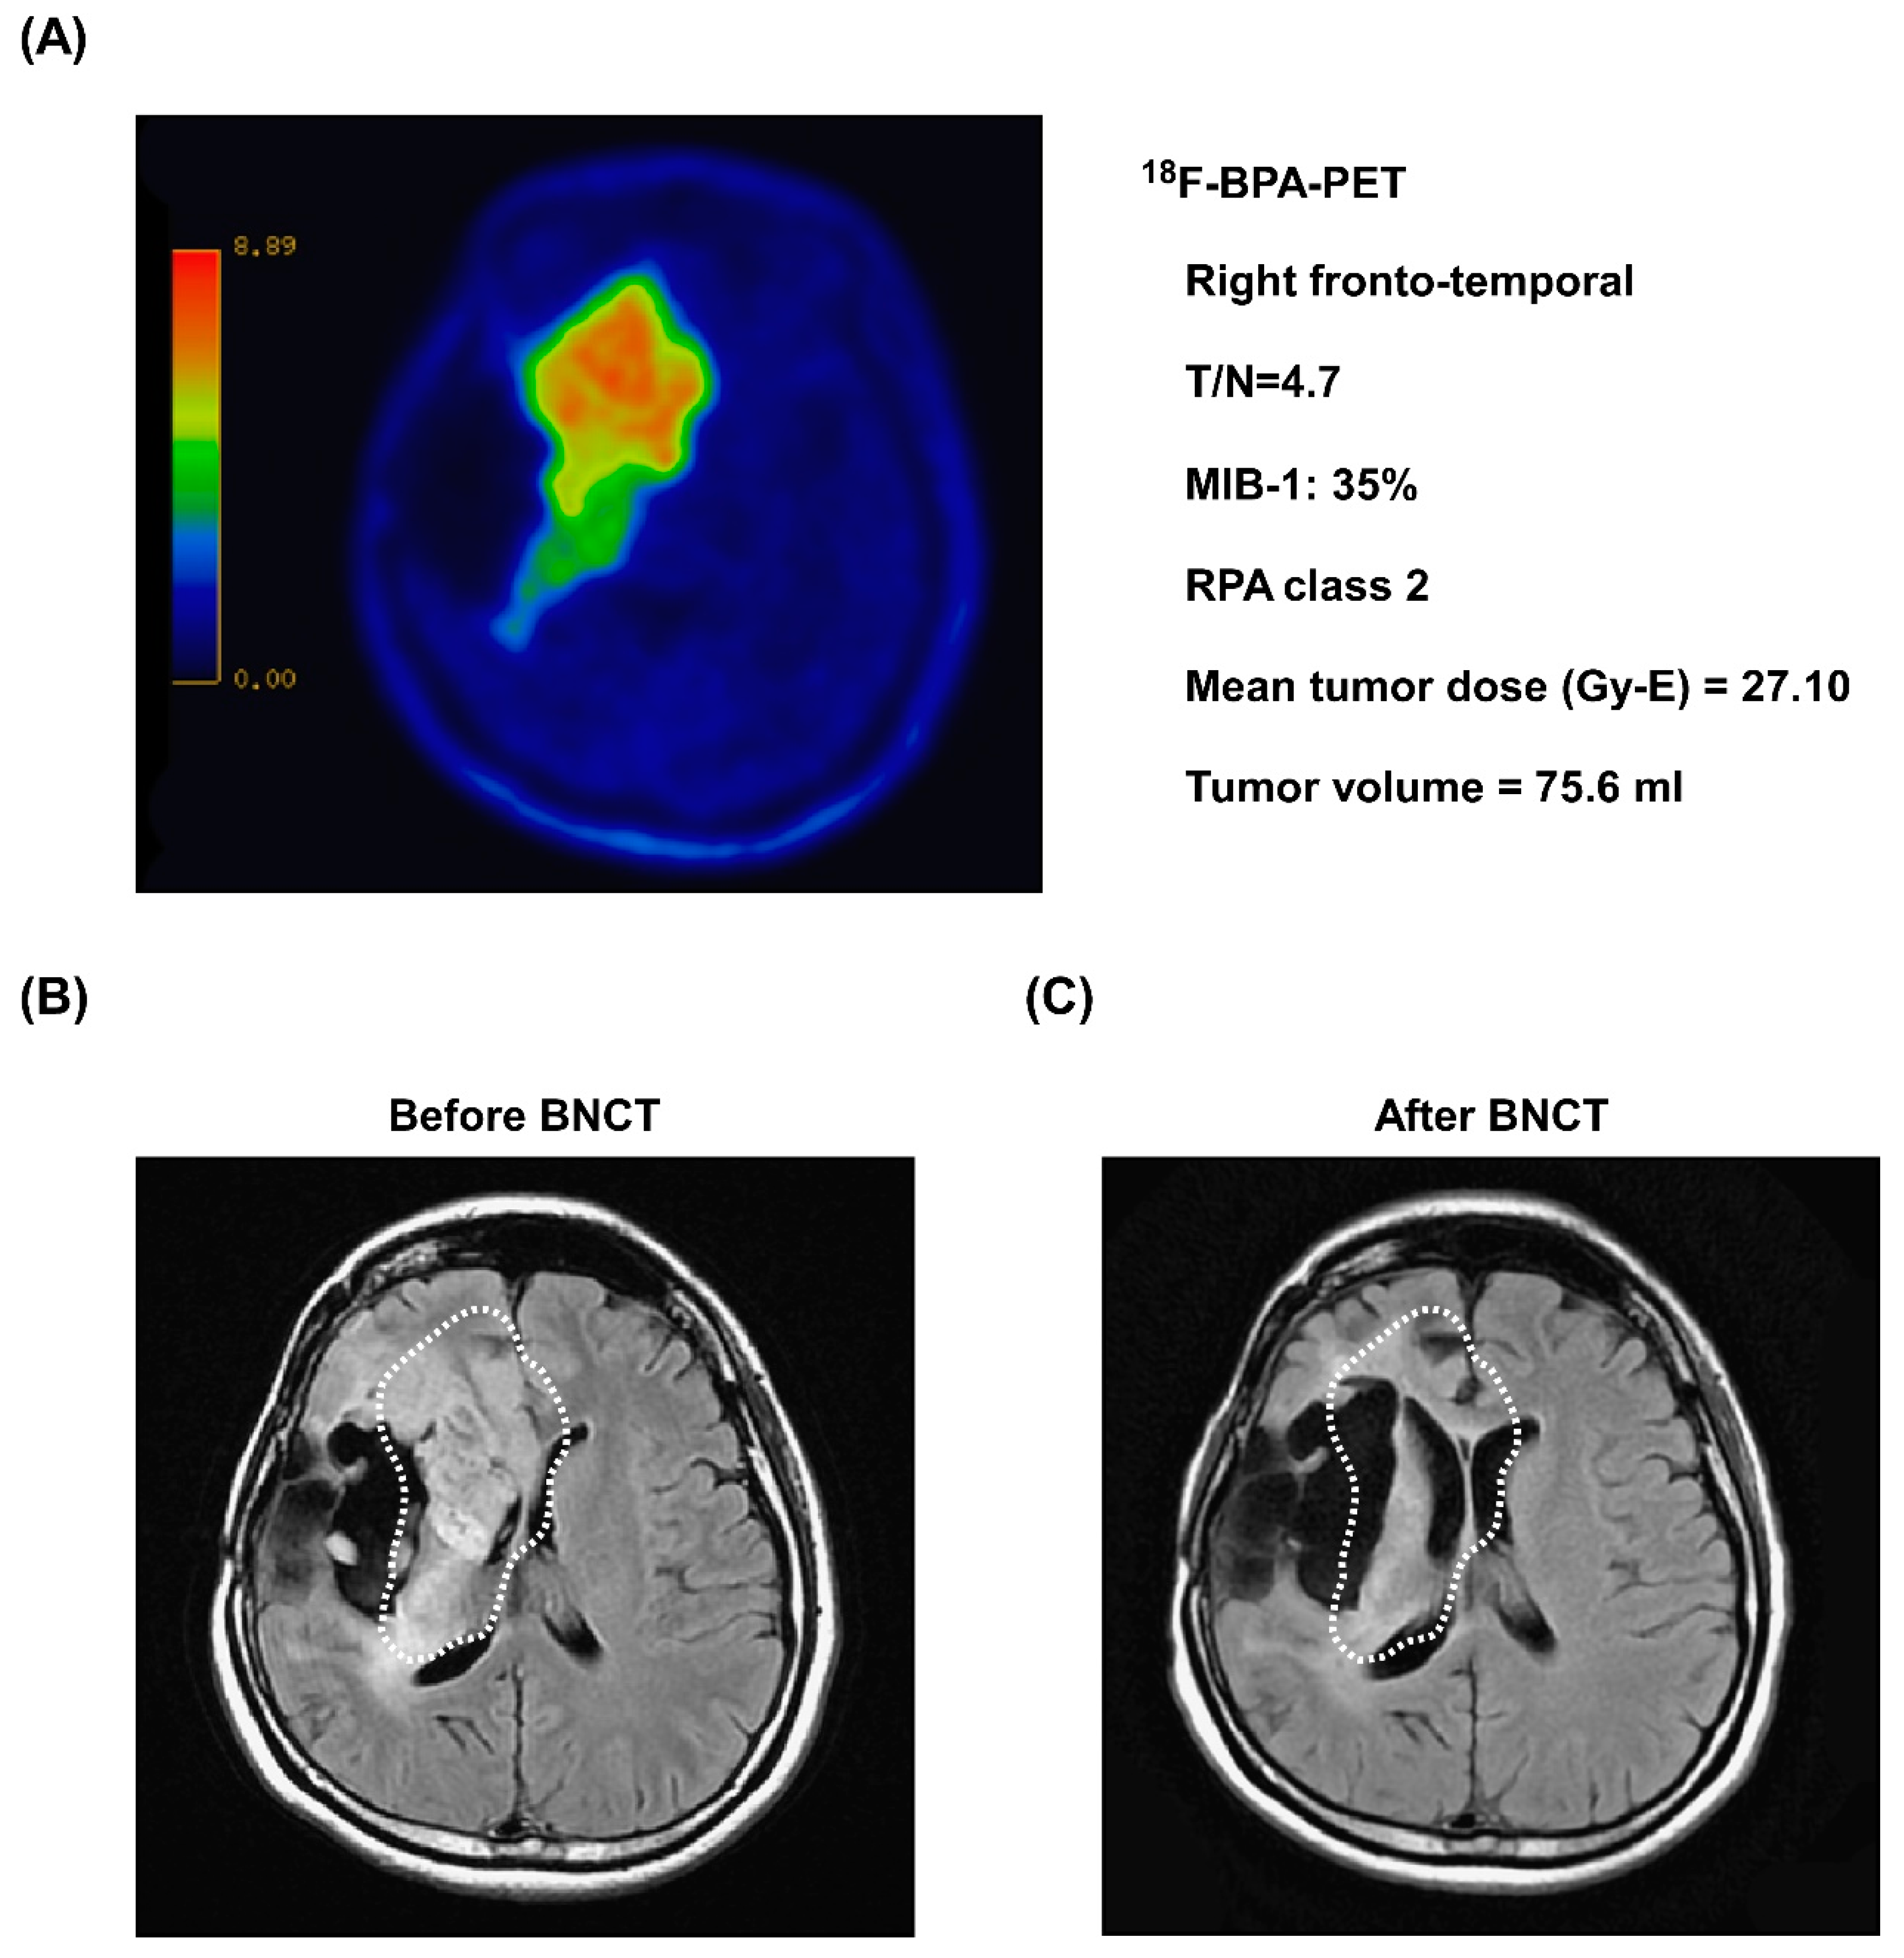

3.5. Representative Case